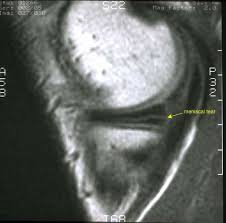

What to do when your knee locks: When the meniscus is torn, the torn portion can flap into the joint and block motion similar to how a loose body may also block motion. I have some looseness of my left knee from a sports injury that happened almost 25 years ago that has left me with a torn meniscus. Dec 21, 2018 · tears of the meniscus can also cause the knee to lock. These sometimes can cause some catching or alter the motion of the knee.

If that is the case then those would be the rare type of tear that actually would need surgery. I have some looseness of my left knee from a sports injury that happened almost 25 years ago that has left me with a torn meniscus. What to do when your knee locks: These sometimes can cause some catching or alter the motion of the knee. When the meniscus is torn, the torn portion can flap into the joint and block motion similar to how a loose body may also block motion. A locked knee due to meniscus tear can be terribly painful and difficult to deal with. If your knee locks suddenly and will not unlock, get help and call your physician or go to your nearest emergency department. Dec 21, 2018 · tears of the meniscus can also cause the knee to lock.